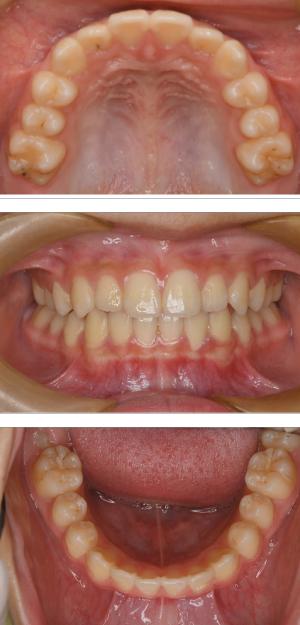

バイオブロック矯正(顎顔面口腔育成治療)

矯正治療は大人になって始めるよりも子どもの頃から始めた方が確実に良い結果をもたらします。成長が盛んな子供の時期に、顎や顔の成長を利用しながら治療ができる大きなメリットがあるからです。当院では、非抜歯矯正を推奨しておりバイオブロック矯正を取り入れています。

バイオブロック矯正の考え方は歯並びが悪くなる原因にアプローチする治療法になります。

舌の位置や口呼吸から乱れてしまった下顎の後退を正し、顎顔面が本来あるべき位置へと誘導させていく治療です。

バイオブロック装置の効果

- お顔立ちが本来の成長へと導かれる(健康的な美しい顔貌)

- 歯並びの改善

- 口呼吸の改善